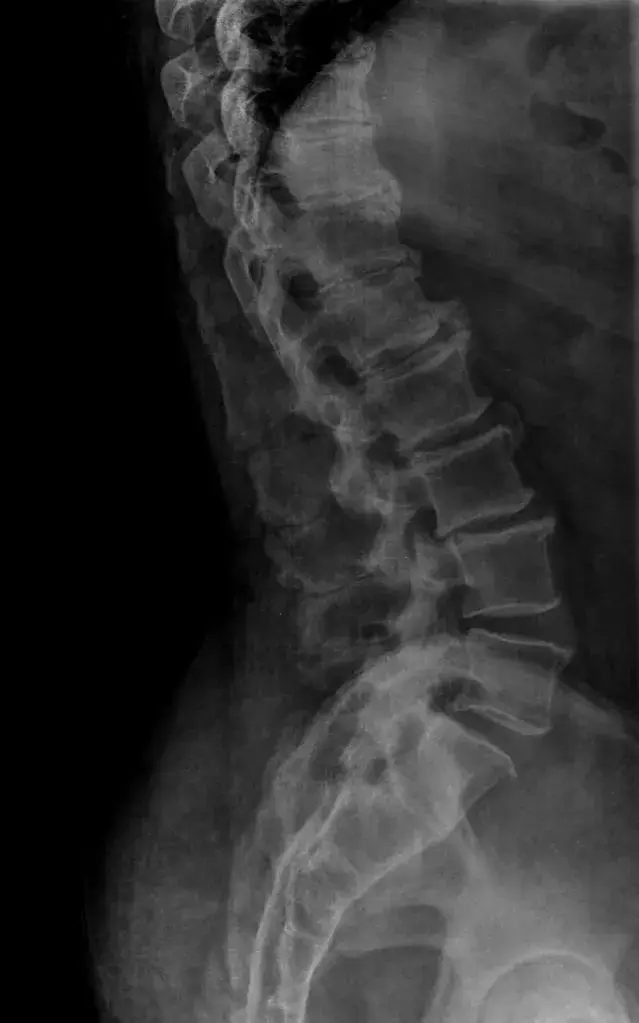

Kissing Xray

Diagnosis

Evaluation begins with a detailed medical history and physical examination. You describe your pain pattern and aggravating movements.

Spinal extension often reproduces symptoms. Flexion often reduces discomfort.

Imaging confirms the diagnosis.

• X rays show contact between spinous processes

• CT scans identify bony degeneration

• MRI evaluates soft tissue inflammation and early degenerative change

MRI provides the clearest view of interspinous soft tissue changes and detects the condition in earlier stages.